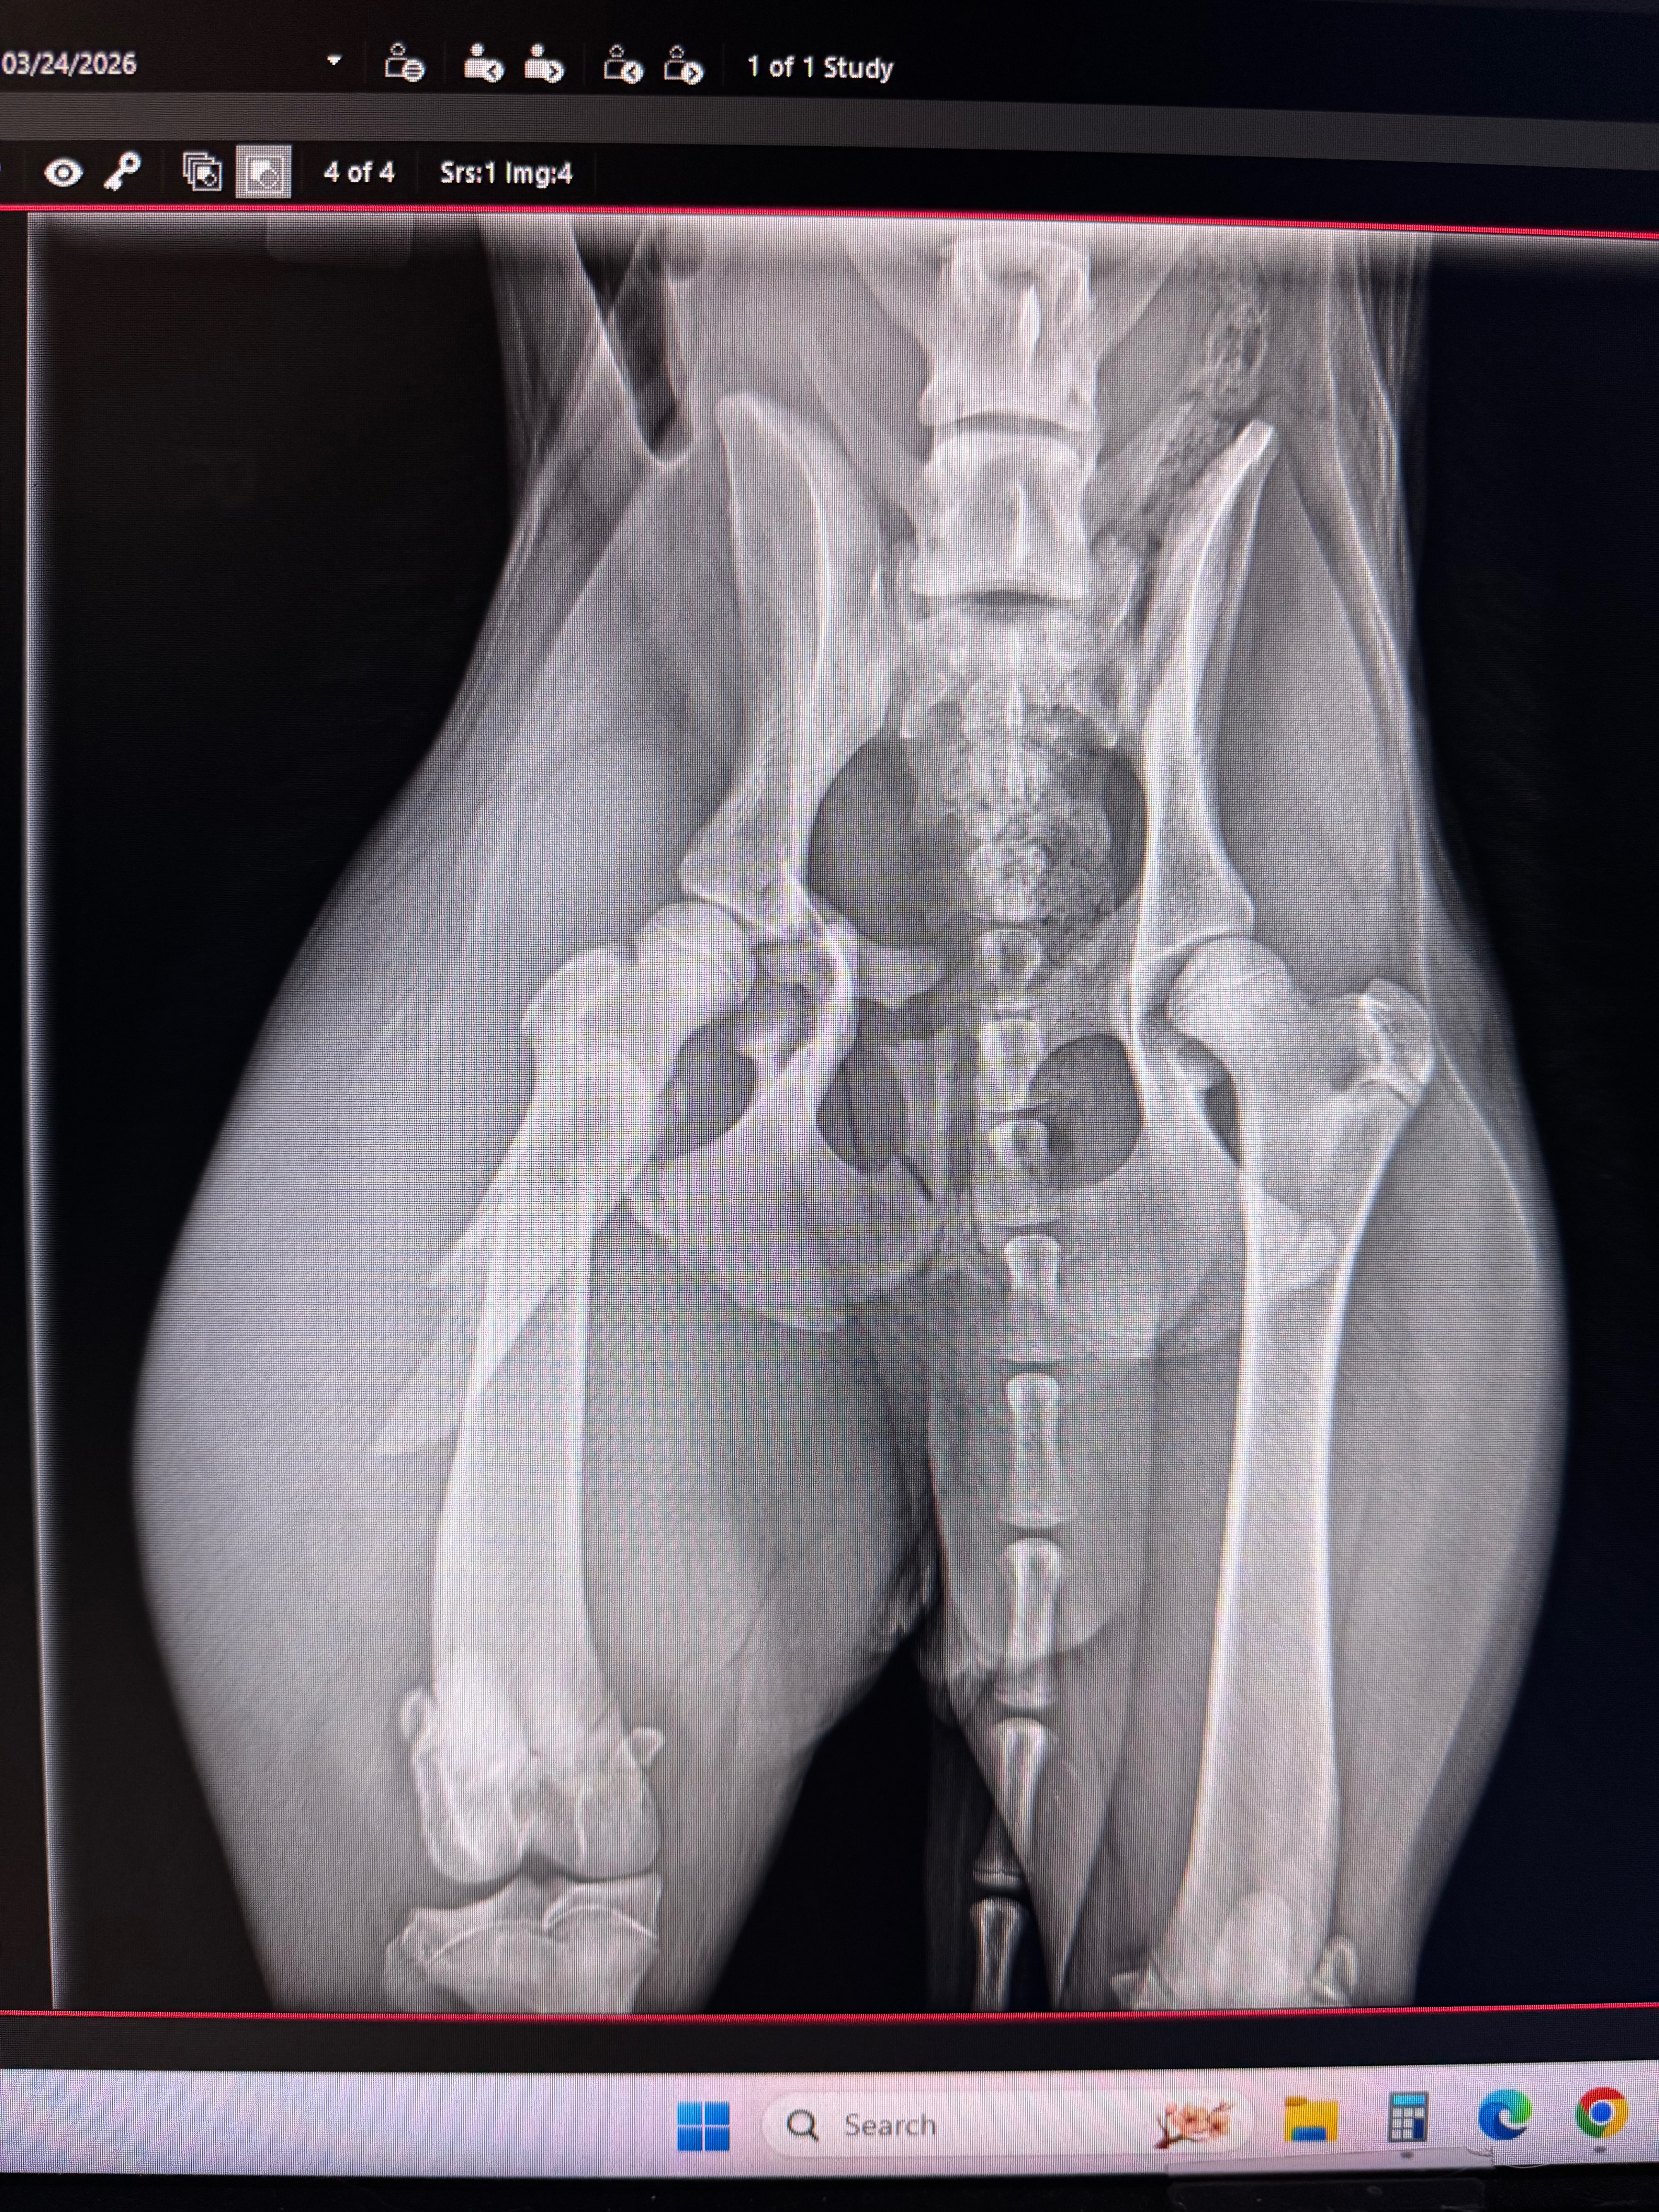

My pet is facing a heartbreaking decision between having her leg amputated or being put down. She has broke 3 different parts of her leg and would need extensive surgery to even be able to think about walking. She's only 6 months old, has already survived parvovirus and this situation has just come on so suddenly. She has brought so much joy and love into our lives in such a short time, and it’s heartbreaking to think of losing her so soon. We never expected to be in this position, but we are determined to do everything we can to give her a fighting chance.

The funds raised will go directly toward her surgery, aftercare, and physical therapy. We want to make sure she has the opportunity to recover and thrive, despite the challenges she’s facing. We do feel since she's young she can make the adjustment to live as a 3 legged baby. Your support will help cover the medical costs, provide her with the care she needs to heal, and give her the best possible quality of life moving forward. Every little bit helps, and your kindness can truly make a difference for her.